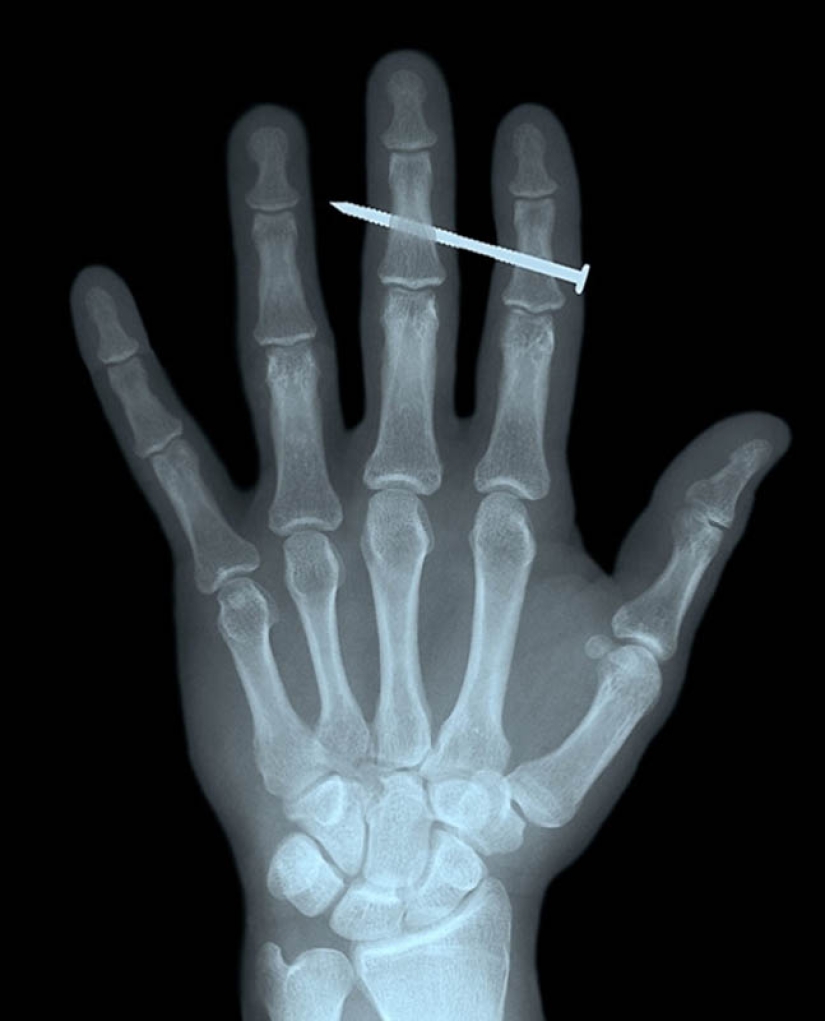

4. A nail in the bones of the index and middle fingers of an adult male.